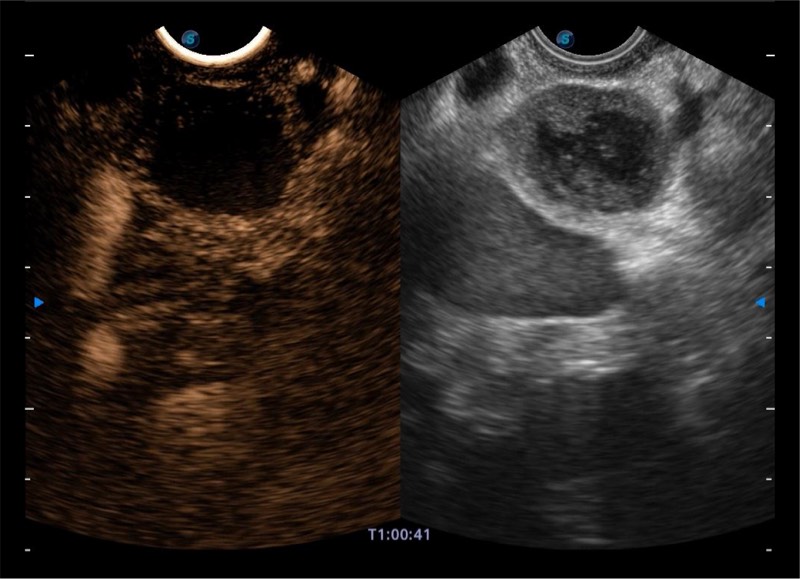

搭载百万级CMOS成像技术

及自主研发凸阵换能器,

可呈现优质的内镜和超声画面

基于二十年的超声技术积累,环球UG官网提供了最新一代的独立超声主机,在提供高质量图像的同时满足多学科使用。具备常见多普勒技术并提供弹性成像、声学造影等高端影像技术。新一代传感器具有更强的抗干扰能力并减少图像伪影。